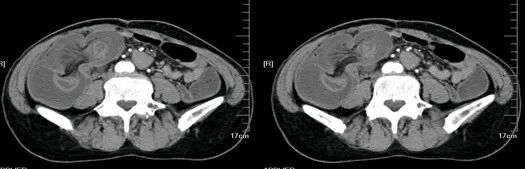

大肠癌

大肠癌是常见的恶性肿瘤,包括结肠癌和直肠癌。大肠癌的发病率从高到低依次为直肠、乙状结肠、盲肠、升结肠、降结肠及横结肠,近年有向近端(右半结肠)发展的趋势。其发病与生活方式、遗传、大肠腺瘤等关系密切。发病年龄趋老年化,男女之比为1.65:1。

升结肠癌并广泛转移

升结肠癌

升结肠癌并肝转移